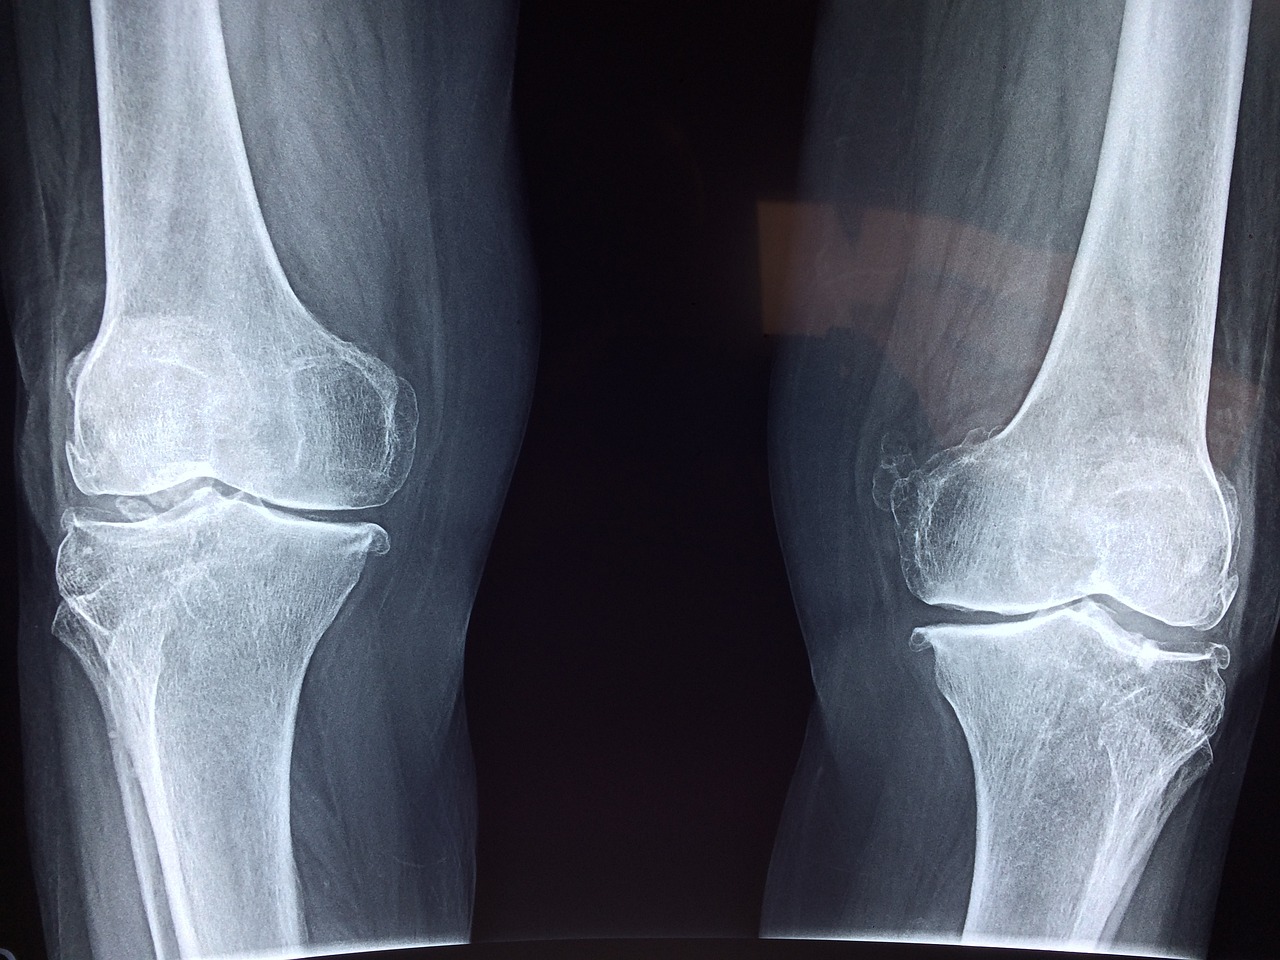

류마티스 관절염은 면역체계가 실수로 관절을 둘러싸는 막의 내막인 윤활막을 공격하는 자가면역 질환입니다. 이 끊임없는 공격은 염증을 유발해 통증과 부기를 일으키고, 효과적으로 관리하지 않으면 결국 관절 손상으로 이어집니다. 정확한 원인은 아직 밝혀지지 않았지만 유전적, 환경적, 호르몬적 요인이 복합적으로 작용한 것으로 추정됩니다.

류미타스 관절염은 종종 점진적으로 존재를 드러냅니다. 초기 증상에는 관절 통증, 경직 및 붓기가 포함될 수 있으며, 특히 아침 또는 활동하지 않는 기간 이후에 발생할 수 있습니다. 질병이 진행됨에 따라 피로, 발열 및 관절 기형이 나타날 수 있습니다. 적절한 시기에 개입하고 잠재적인 관절 손상을 완화하려면 이러한 징후를 조기에 인식하는 것이 중요합니다.